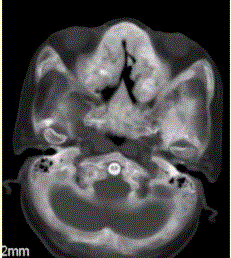

问题 患者女,25岁,左侧面部肿块,突眼10余年。CT表现如下图。 临床拟诊为

选项 A.畸形性骨炎 B.黄色瘤 C.骨纤维异常增生症 D.骨瘤 E.骨囊肿 F.内生软骨瘤

答案 C